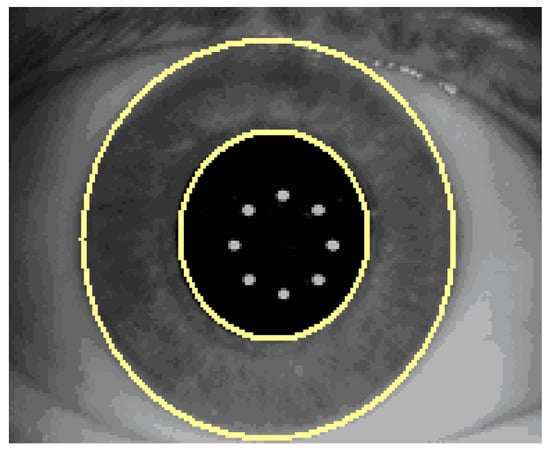

By introducing the rotational eye tracker in the Technolas 217z100P™ the already approved X/Y tracker, which compensates actively for transversal movements of the eye, will be upgraded to compensate for misalignments in rotation. While it uses the acquired iris images only, additional objectively acquired information is needed to provide a rotational tracking capability. The 217z100P rotational tracker module is based on iris pattern recognition technology. It is well known that iris patterns are similar to finger prints with unique biometric properties of the individual. By using the appropriate technology, not only the individual eye can be recognized but also specific match parameters—such as rotational misalignment between two images of the same iris—can be obtained. The basic data used to analyze iris patterns are acquired infrared images of the iris. With special image processing and normalization technologies, the iris images are processed to account for differences in illumination conditions (large and small pupils) or even from different systems (such as Zywave wavefront sensor and laser system). The Zywave wavefront sensor is a diagnostic system which utilizes the same wavelength to acquire an Infrared (IR) image forms, the eye, and the corresponding iris [8]. Finally, the process described above results in a digital code which is created as follows: determine automatically pupil boundary and limbus boundary of the reference image (Figure 5).

Figure 5. Pupil and limbus boundary recognition of the reference image.